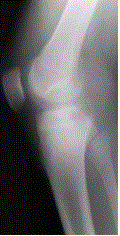

患者男,15岁。右膝X线平片和CT检查见下图。病变发生部位是A.骨端B.干骺端C.骨骺D.骨干E.关节腔

问题 患者男,15岁。右膝X线平片和CT检查见下图。 病变发生部位是

选项 A.骨端 B.干骺端 C.骨骺 D.骨干 E.关节腔

答案 C